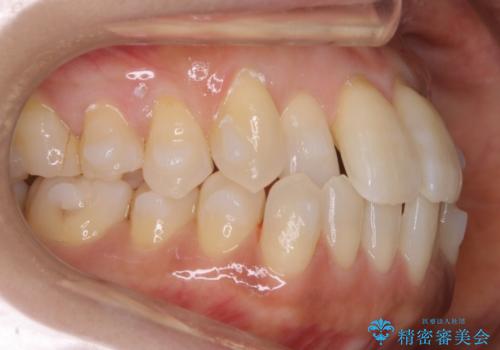

拡大とIPR

歯列の幅を拡大することにより作れるスペースは想像より大きく、実際に拡大だけでガタつきが治せるというケースもあります。

その他の歯のガタつきをとるためのスペース作りの方法の一つにディスキング(IPR)という方法があります。

歯と歯の間を一ケ所あたり最大0.5mmまでの範囲内で削ることで歯自体が少し小さくなり、それにより作られるスペースを数ヶ所分合わせることで合計で数mmの大きなスペースが作れるという方法です。

当院ではなるべく歯の機能や見た目に影響の出ないよう、作業時に拡大鏡の使用や削るタイミングの微調整を行っています。